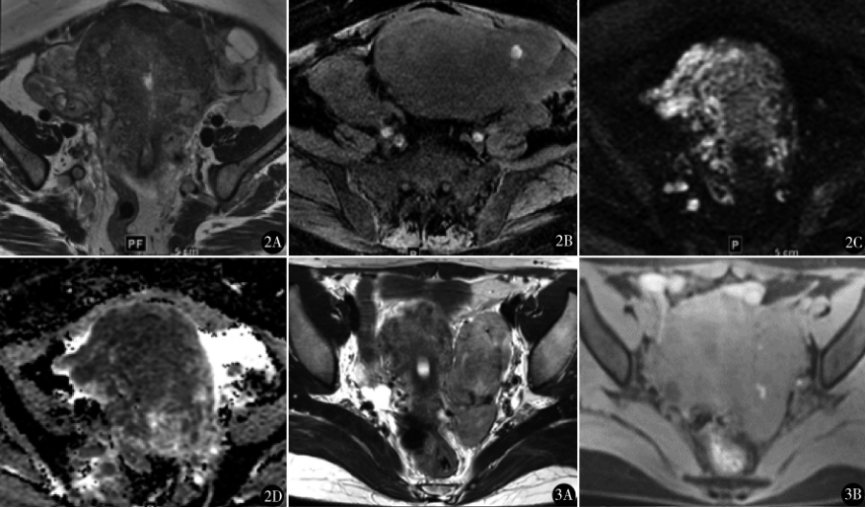

图2 低级别子宫内膜间质肉瘤(ESS)MR平扫:患者80岁,发现子宫肌瘤12年,阴道不规则 出血2个月,行全子宫和双附件切除术,术后病理为低级别子宫内膜间质肉瘤。 A.轴位T2WI 显示肿瘤为不规则高信号肿物,边界不清,占据大部分子宫肌层,并可见“蠕虫样延伸”征,累及 宫旁及附件;B.轴位T1WI显示肿瘤内少许高信号;C.肿瘤DWI信号明显增高;D.ADC图为 明显低信号,即为DWI明显弥散受限区

图3 富于细胞性平滑肌瘤(CL)MR平扫:患者33 岁,外院子宫肌瘤剔除术后11个月,发现盆腔包块1个月,行子宫肌瘤剔除术,术后病理富于细胞性平滑肌瘤。 A.轴位T2WI肿瘤为左宫旁卵圆形高信号肿物,边界清晰,未见“蠕虫样延伸” 征;B.轴位T1WI显示肿瘤内少许高信号;C.肿瘤DWI信号增高;D.ADC图为明显低信号,即为DWI明显弥散受限区